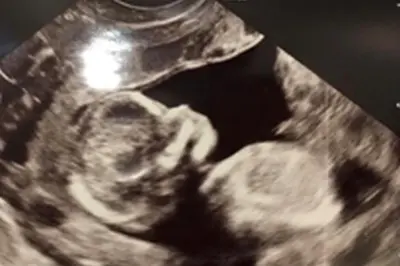

Durch modernste Geräte inklusive der 3D- und 4D-Technologie werden alle systematischen Ultraschalluntersuchungen zum Ausschluss von Fehlbildungen in jedem Schwangerschaftsstadium durchgeführt. In jedem Drittel der Schwangerschaft bieten wir ausführliche Ultraschalluntersuchungen, sog. Screenings an. Beim Screening im I Trimenon (1. Drittel) ist es auf Wunsch der Schwangeren möglich, den nicht-invasiven Bitest durchzuführen, welcher ein Verfahren zur Risikoberechnung einer chromosomalen Störung des Kindes ist und sich aus Messung der Nackentransparenz des Kindes mittels Ultraschall und einer mütterlichen Blutuntersuchung zusammensetzt. Zusätzlich kann zu diesem Zeitpunkt das Risiko für die Entwicklung einer Präeklampsie (Gestose) im Laufe der Schwangerschaft ermittelt werden. Bei Verdacht auf Fehlbildungen des Kindes können in unserem Haus Untersuchungen der Stufe I und Stufe II durchgeführt werden, eventuelle weiterführende Diagnostik wie Durchführung des NIPT- Tests sowie invasive Verfahren wie Amniozentese und CVS werden bei entsprechender Indikation von uns organisiert.

Einmal in der Woche findet unsere fetale Echokardiographie- Sprechstunde statt (Herzdiagnostik des Kindes), welche in der Frühschwangerschaft und um die 20. Schwangerschaftswoche in spezifischen Fällen indiziert wird.